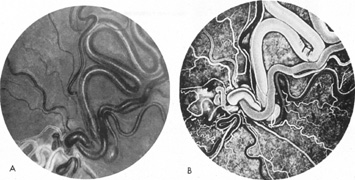

In some persons, the cavernous sinuses have existing or potential connections to the deep venous system of the brain. Indeed, this may be the preferential route of venous drainage from all or part of the cavernous basal sinus complex. Therefore, the clinical appearance of orbital venous hypertension associated with a cavernous dAVM may be relatively minimal, but arterialized flow is transmitted instead chiefly via venous dural channels draining the medial aspects of the temporal lobes and the basal vein of Rosenthal. The latter drains an extensive deep parenchymal territory, including part of the posterior fossa. This effluent pattern explains how some cavernous dAVMs or CCFs present with relatively minor outward physical signs but with serious complications from cortical venous hypertension (Fig. 18), elevated intracranial pressure (a form of secondary pseudotumor cerebri syndrome; see Chapter 5, Part II), temporal lobe seizures, brain parenchymal hemorrhage caused by venous infarction or venous rupture (Fig. 19), or edema of the posterior fossa structures.119

Fig. 18. A 25-year-old man developed severe right-sided proptosis and a loud bruit at the time of a vehicular accident. Lateral projection of the right internal carotid artery in the early arterial phase (A) and late arterial phase (B) in anteroposterior projection demonstrate immediate opacification of the superior and inferior ophthalmic veins (straight arrows), the inferior petrosal sinuses (curved arrows) and of the deep parenchymal veins of the right hemisphere (open curved arrows). The fistula was related to a large carotid laceration involving the cavernous and supraclinoid segments of the right internal carotid artery. The artery could not be preserved at the time of treatment. C: Latex balloons (open-ended arrowheads) were placed in the fistula and within the carotid artery at the time of treatment. (Courtesy of Frank Huang-Hellinger)

Fig. 19. A 30-year-old woman presented with headaches. Lateral views of left (A) and right (B) internal carotid arteriograms demonstrate developmental venous malformation of the cribriform plate supplied by both ophthalmic arteries. Note subarachnoid veins of the anterior cranial fossa (curved arrows). In addition, the right ophthalmic artery (B) has a cavernous origin (arrow), a vestige of the dorsal ophthalmic artery that usually atrophies in fetal development.